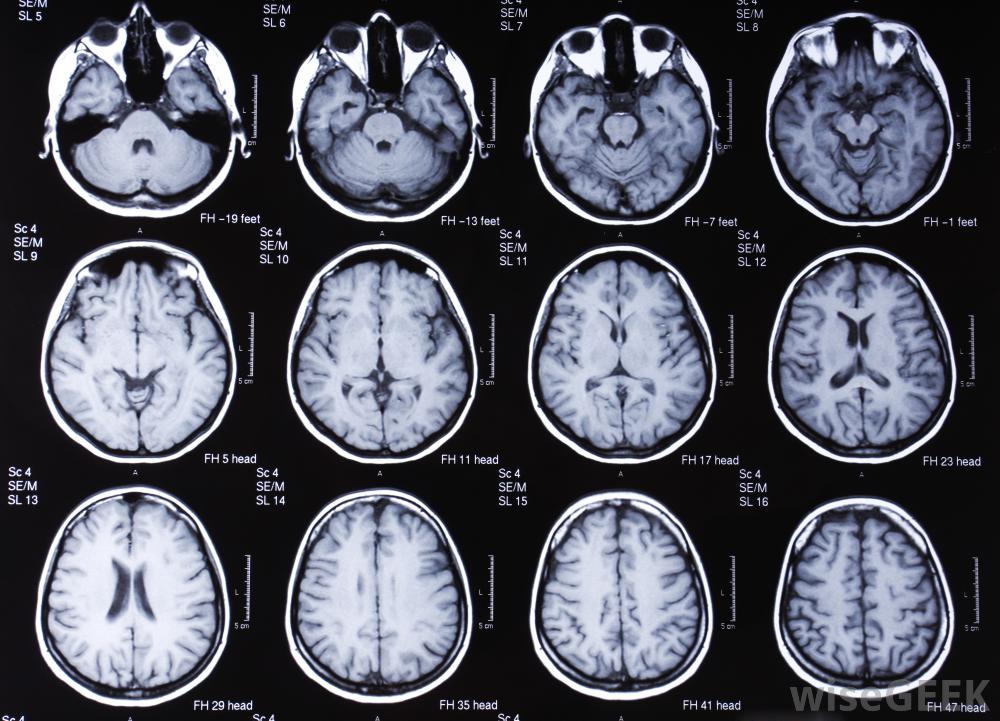

无对比度的脑部核磁共振扫描核磁共振成像机利用人体内粒子的磁特性来形成图像。核磁共振扫描是医生可用的最详细的诊断成像形式之一。核磁共振扫描的好处是不需要使用电离辐射,可能会对患者造成潜在伤害,尽管机器的制造和维护成本高昂。

大多数核磁共振检查都是在没有对比的情况下进行的标准的核磁共振扫描被称为无对比剂的核磁共振成像。这意味着磁共振成像机可以对所需区域进行成像,而无需将造影剂注入人体。在大多数情况下,除非受影响的区域很小或很难看到,否则无对比度的核磁共振成像是检查身体内部问题所必需的

带对比度的MRI可以帮助医生测量小肿瘤,以确定治疗是否正常。无对比度的MRI可用于身体大部分部位。一些最常见的部位需要核磁共振扫描包括大脑和脊髓。关节也经常被扫描以发现损伤的软骨和撕裂的韧带。

无对比度的MRI扫描提供了非常详细的信息,尽管机器的制造和维护成本很高在某些情况下,医生可能需要使用增强磁共振成像(MRI)来更详细地观察身体的某个特定区域。这需要在扫描过程中通过单次注射或静脉滴注将对比剂"染料"注射到身体内。对比剂的目的是识别体内的任何活动性问题为了提高图像的灵敏度,通常使用无对比度的MRIs来获得大脑或脊髓的精确图像